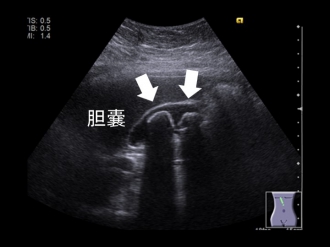

胆嚢結石